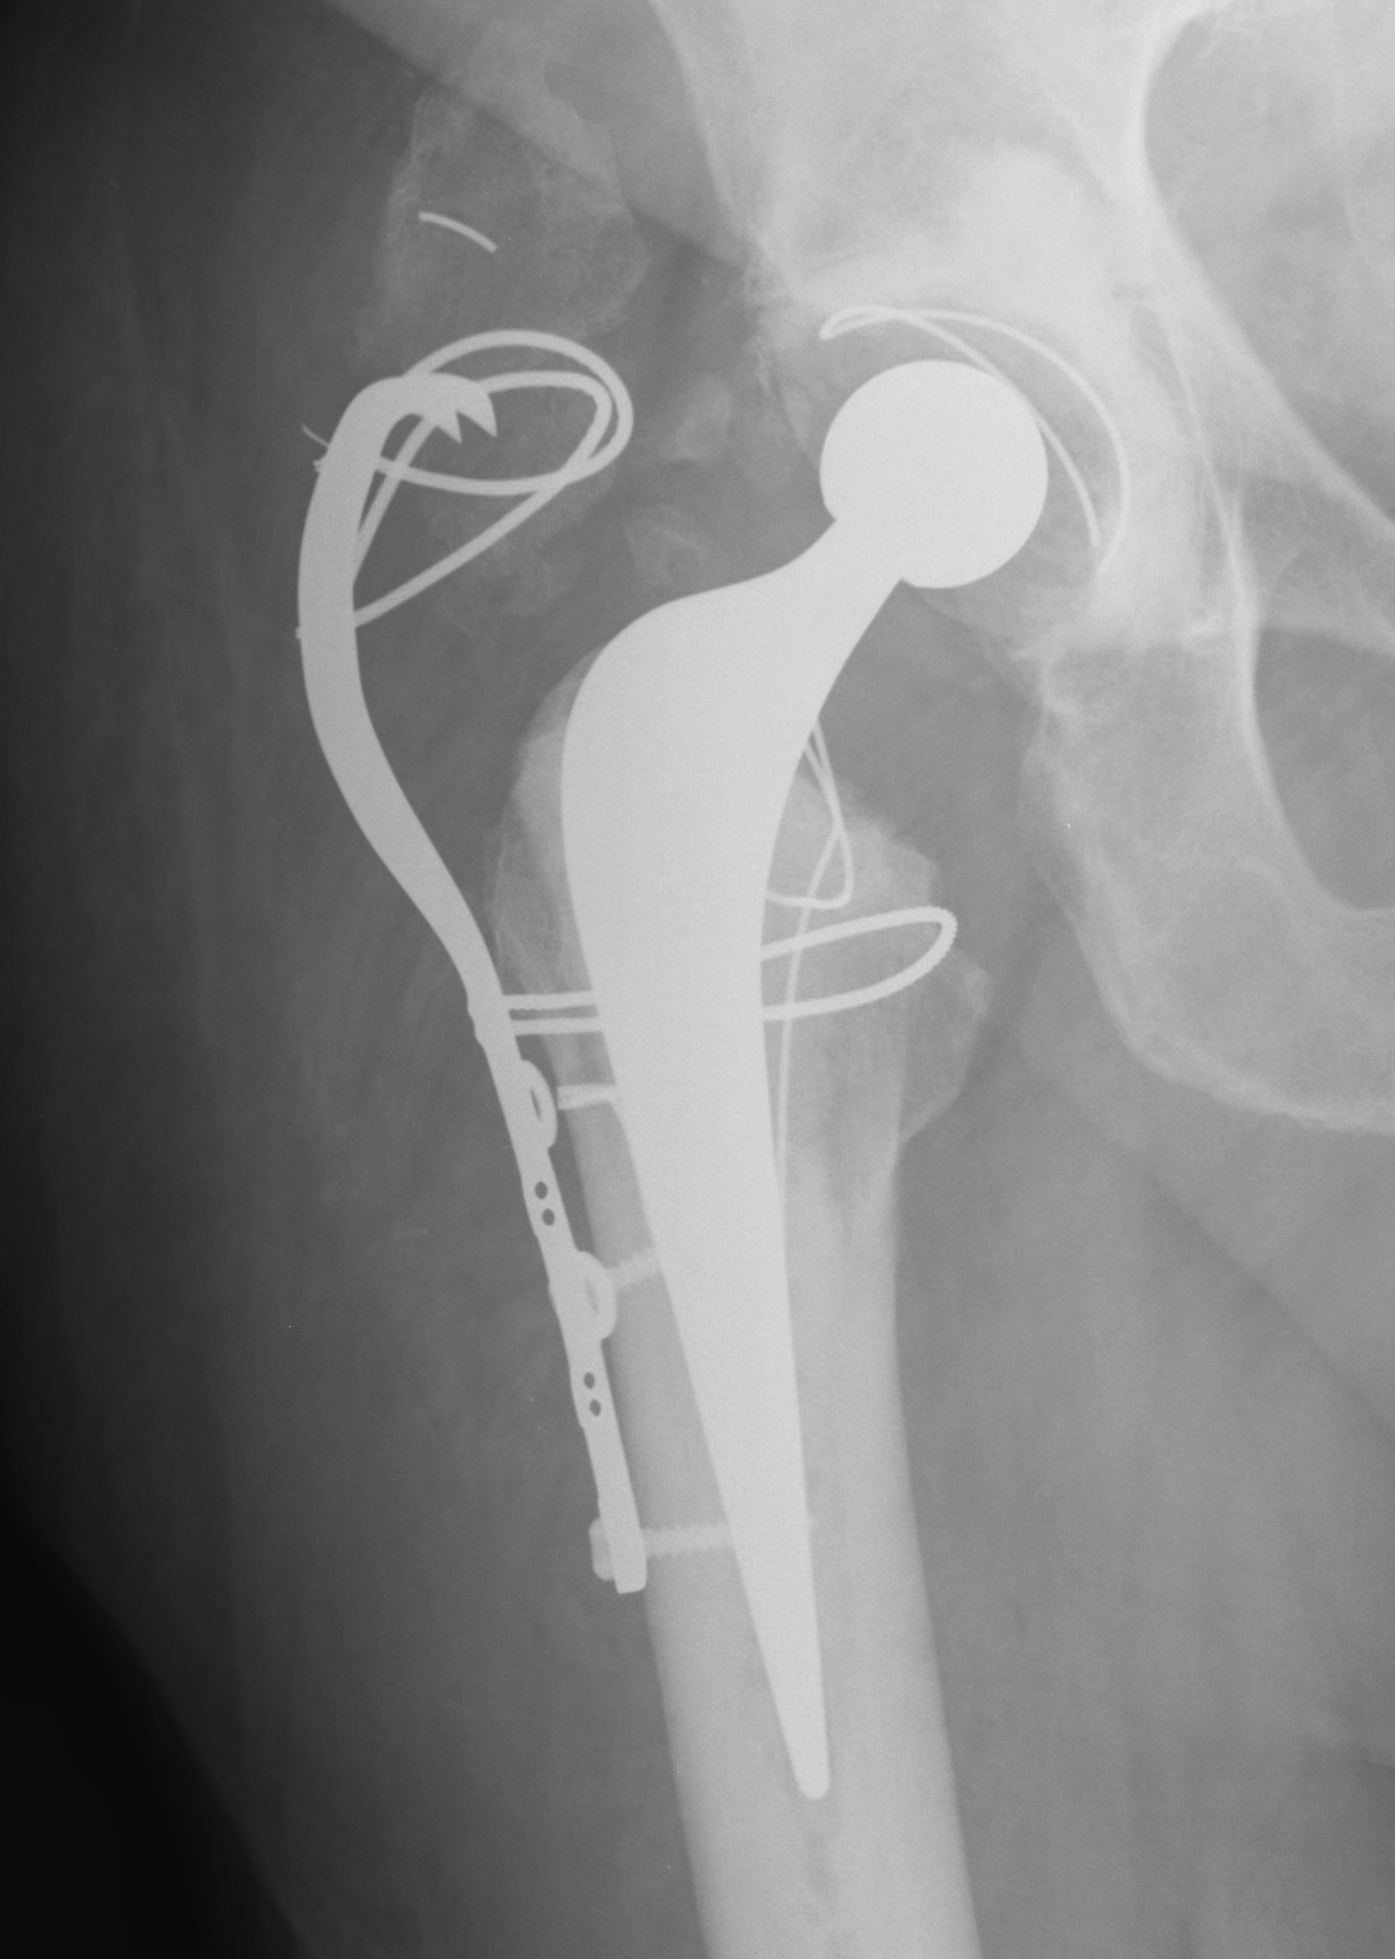

Extended Trochanteric osteotomy

Concept

Osteotomy lateral 1/3 to 1/2 of trochanter & femur

- posterior to anterior longitudinal cut

- short distal transverse cut

- levers / hinges open anteriorly

- maintains anterior vasculature / muscle attachment

Technique ETO

Length

- measured from tip GT

- 2 – 15 cm long

- determined from preoperative template

- need to preserve diaphysis if using distal press fit uncemented stem

Osteotomy

- use drill holes to mark osteotomy

- drill both cortices

- thin oscillating saw

- cut down through anterior and posterior femur in line with GT

- through both cortices

- transverse cut distally through 1/3 diameter

- lever open

Fixation

- 3 x cerclage cables

- protect sciatic nerve / palpate / pass wires posterior to anterior

- submuscular

Results

98 – 100% union rate by 6/12